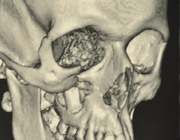

Fracture de la pommette droite et du plancher de l'orbite- cliché scannographique 3D pré-opératoire: